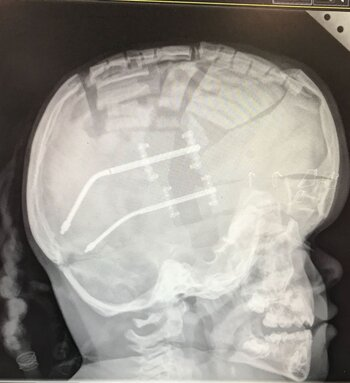

Her first surgery was at nine months old, to help correct the shape of her skull by cutting a section away and fitting bolts. My wife and I then had to turn a bolt each morning for weeks to slowly move the back of her skull out and stretch her scalp. This made a significant difference but was step one of many.

The following summer we noticed her behaviour and physical abilities were changing – the pressure on her brain was building again. A drain called a shunt was inserted into her brain. This made a huge difference but unfortunately blockages were and are still common.